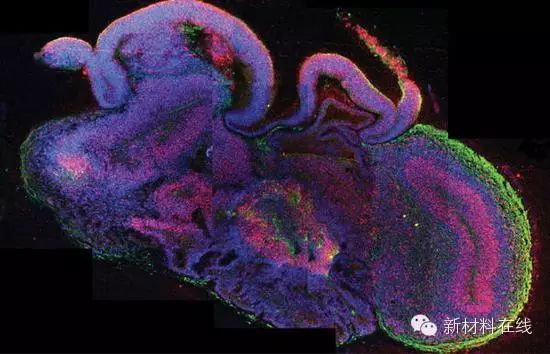

8.脑细胞团培育

技术突破:通过这一技术,科学家可以在实验室中利用人类干细胞培育出三维的神经元集群。

重要意义:研究人员需要通过新方式去理解大脑疾病,并试验可能的治疗手段。

关键人物:分子生物学技术研究院的麦德林·兰卡斯特(Madeline Lancaster)和尤尔根·诺布里奇(Jurgen Knoblich),以及麻省综合医院的鲁道夫·坦齐(Rudolph Tanzi)和Kim Doo Yeon。

技术成熟时间:现在